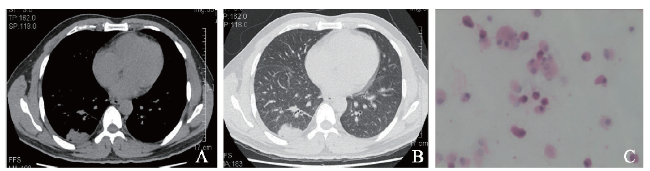

例1 患者女,66岁。因反复咳嗽3月余、加重伴少量咳白痰1个月于2014年4月20日收入我科。患者3个月前受凉后反复咳嗽,未予重视,近1个月来加重并伴咳白痰,无发热,有乏力,睡眠差,起病以来体质量下降约5 kg。既往史及个人史无特殊。入院体格检查:体温36.8 ℃,脉搏90次/分,呼吸20次/分,血压120/70 mm Hg(1 mm Hg=0.133 kPa)。生命体征平稳,双肺呼吸音清,可闻及Velcro啰音。入院后完善检查,血常规:血红蛋白132 g/L,白细胞5.51×109/L,嗜酸性粒细胞0.13×109/L,血小板251×109/L。肿瘤标志物癌胚抗原6.9 μg/L,细胞角蛋白19片段测定、神经元特异性烯醇化酶测定、甲胎蛋白等均未见明显异常,免疫标志物均未见异常。予头孢哌酮钠-舒巴坦钠3.0 g、每日2次,莫西沙星0.4 g/d,哌拉西林钠-他唑巴坦钠4.5 g、每日2次静脉滴注,患者症状无好转。4月24日完善纤维支气管镜(纤支镜)检查,送BAL病理检查见活动性鞭虫,住院期间经甲硝唑0.5 g每日2次联合复方磺胺甲恶唑0.8 g每日3次抗鞭虫治疗后症状好转。4月29日CT示双肺可见弥漫斑片状密度增高影,边缘模糊、密度不均,部分融合成片,大部分为磨玻璃样密度,呈地图状改变,内见空气支气管征(图1A、B)。因双肺弥漫渗出性病变,考虑为肺泡蛋白沉积症可能性大。5月5日BAL苏木素-伊红(HE)染色示大量泡沫样细胞(图1C)、组织细胞,少量纤毛柱状上皮细胞、淋巴细胞、中性粒细胞及少量散在退变核异质细胞,个别异常核分裂;过碘酸雪夫(PAS)染色(-)。病理活组织检查(活检)(左舌叶和下叶肺组织)送检组织3微粒:镜下为少许肺组织,部分区域肺泡上皮增生,腺体排列较密集,细胞核浆比例失调,核增大,可见核仁,呈轻 ~ 中度非典型,核分裂未见;免疫组织化学染色(免疫组化)示癌胚抗原(±),Ki-67 < 5%,CK7(+);PAS示肺泡上皮内、间局灶红染物沉积,六胺银(-),抗酸(-)。考虑为肺泡上皮增生丰富活跃,不排除贴壁生长低级别肺腺癌。患者经吸氧、抗感染、平喘、祛痰等治疗症状有所好转后即自动出院,家属未同意进一步肿瘤相关治疗,未再复诊。

图1 例1肺腺癌合并鞭虫感染患者的胸部CT及BAL涂片结果

A:胸部CT纵隔窗;B:胸部CT肺窗;C:BAL涂片(HE染色,×400)